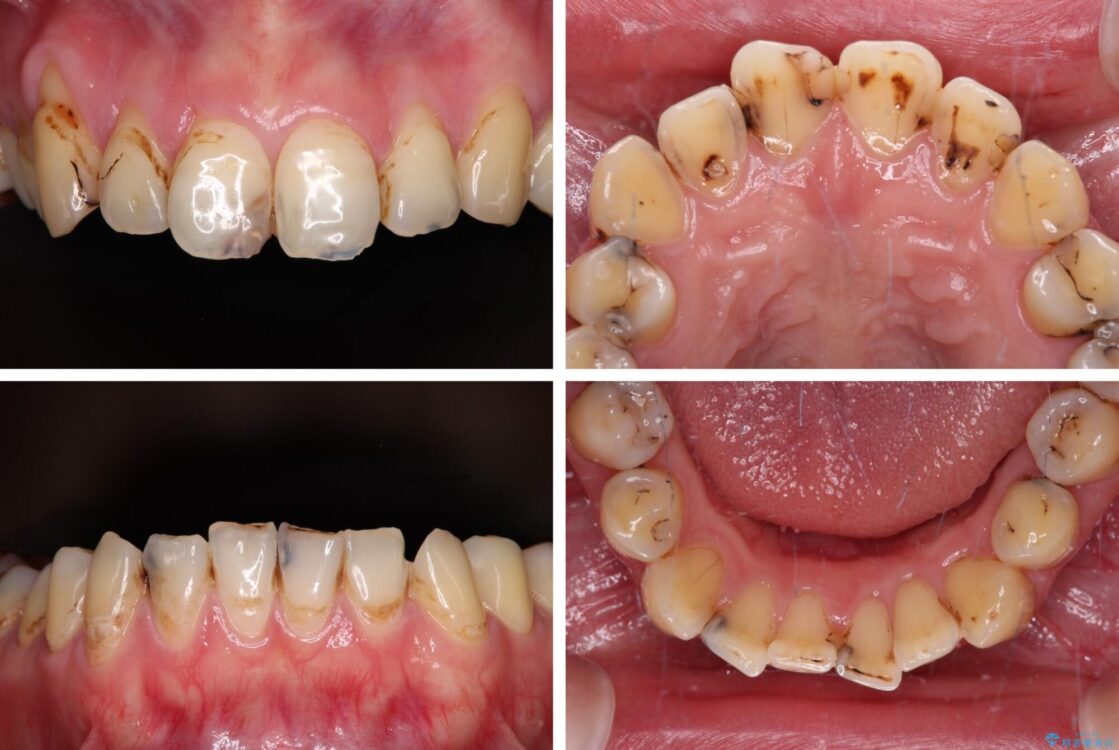

上下前歯や奥歯の虫歯治療を希望して来院された患者様です。

全顎的にむし歯が多く、根管治療の必要な奥歯や、審美的に気になっている前歯を中心にオールセラミッククラウンにて補綴治療を行うこととしました。

上顎前歯は歯肉退縮により歯根が露出していたため、事前に歯肉移植術により根面被覆を行い、その後にオールセラミッククラウンを装着することとしました。

治療前

• むし歯だらけの前歯をオールセラミッククラウンできれいに 治療前画像